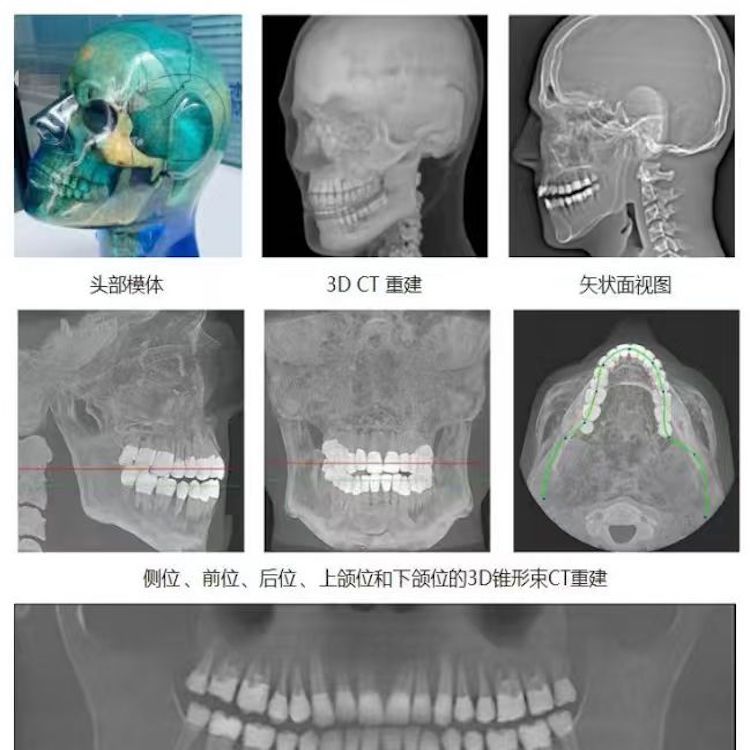

頭部模體是頭部診斷放射學(xué)的參考標(biāo)準(zhǔn),該模體旨在協(xié)助技術(shù)和臨床人員,在大多數(shù)需要精細(xì)解剖細(xì)節(jié)的放射學(xué)程序中選擇、監(jiān)測、培訓(xùn)和驗證掃描參數(shù)。 模體為研究人員、臨床醫(yī)生和技術(shù)人員提供了一致性的工具。它非常適合確定最佳系統(tǒng)設(shè)置、調(diào)試新設(shè)備、監(jiān)測系統(tǒng)性能和培訓(xùn)牙科X射線、全景X射線、CT和錐束CT程序。 這個模體包括一個可調(diào)節(jié)的支架,用于在錐束 CT 或全景X射線系統(tǒng)中定位。模體的下頜略微張開,前牙垂直排列,以復(fù)制正確的咬合引導(dǎo)定位 。 請注意,實際咬合引導(dǎo)無法在這個產(chǎn)品中定位。 頭部模體是由專有組織等效材料制成的。由組織模擬樹脂制成,這些樹脂模擬X射線對人體的衰減特性,適用于CT和治療能量范圍(50keV-25MeV)。 模體在大小和結(jié)構(gòu)上都近似于平均男性頭部 。該模體包括詳細(xì)的3D擬人化解剖結(jié)構(gòu), 包括大腦、骨骼、喉、氣管、鼻竇、鼻腔和牙齒。骨骼包括皮質(zhì)和骨小梁的分離。牙齒包括明顯的牙本質(zhì)、牙釉質(zhì)和包括神經(jīng)的牙根結(jié)構(gòu)。鼻竇完全張開。

頭部模體特點 1. 詳細(xì)的解剖特征; 2. 確定法蘭克福平面以確保正確對齊; 3. 50 keV 至 25 Mev 的組織等效值; 4. 具有六個自由度的定位支架; 5. 包括泡沫內(nèi)襯手提箱; 6. 12個月保修。

功能和應(yīng)用 1. X射線 ,全景X射線 ,CT和錐束CT系統(tǒng); 2. 學(xué)習(xí)如何正確定位頭部以獲得最佳圖像; 3. 測試重建技術(shù)和算法 ,用于植入物規(guī)劃和頜面部重建; 4. 在實施新設(shè)備和新技術(shù)期間培訓(xùn)并評估人員; 5. 驗證圖像質(zhì)量的一致性。